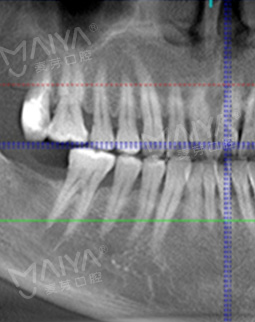

拍了片子,医生指出牙周膜增宽,左上根尖部阴影大,面部有稍微萎缩,为我制定了数字化精确种牙技术,其实也很好奇,现在种牙到底有多精确多快速,和医生约定好了时间,下次直接种牙。